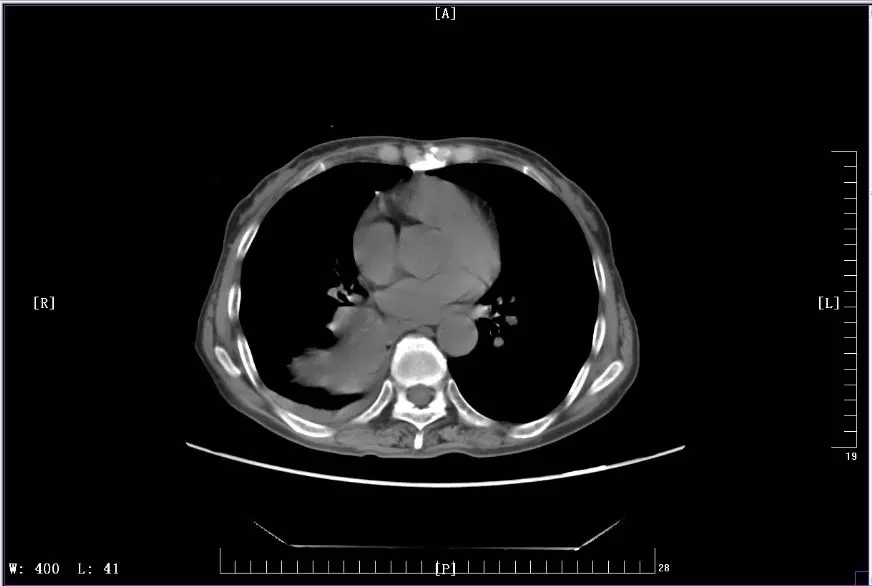

下圖是徐麗參加KEYNOTE-407臨床試驗(yàn)前后CT影像對(duì)比圖:

2018年6月治療中CT影像